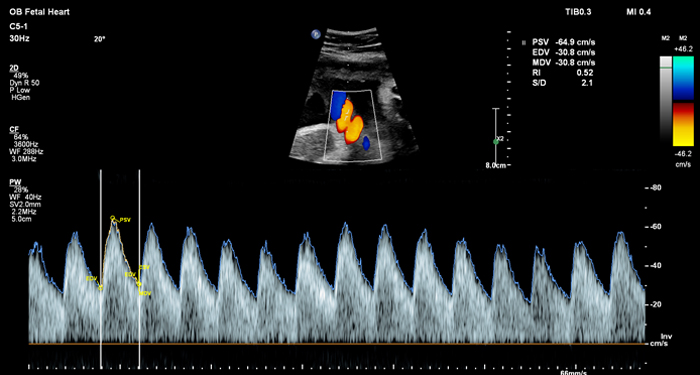

At the touch of a button, the new MaxVue high-definition display brings extraordinary visualisation of anatomy with 1,179,648 additional image pixels compared to a standard 4:3 display format mode. MaxVue enhances ultrasound viewing during interventional procedures and provides 38% more viewing area to optimise the display of dual, side/side, biplane, and scrolling imaging modes.

MaxVue offers a 38% greater viewing area.

MaxVue offers 1,179,648 additional image pixels compared to a standard 4:3 display format mode.